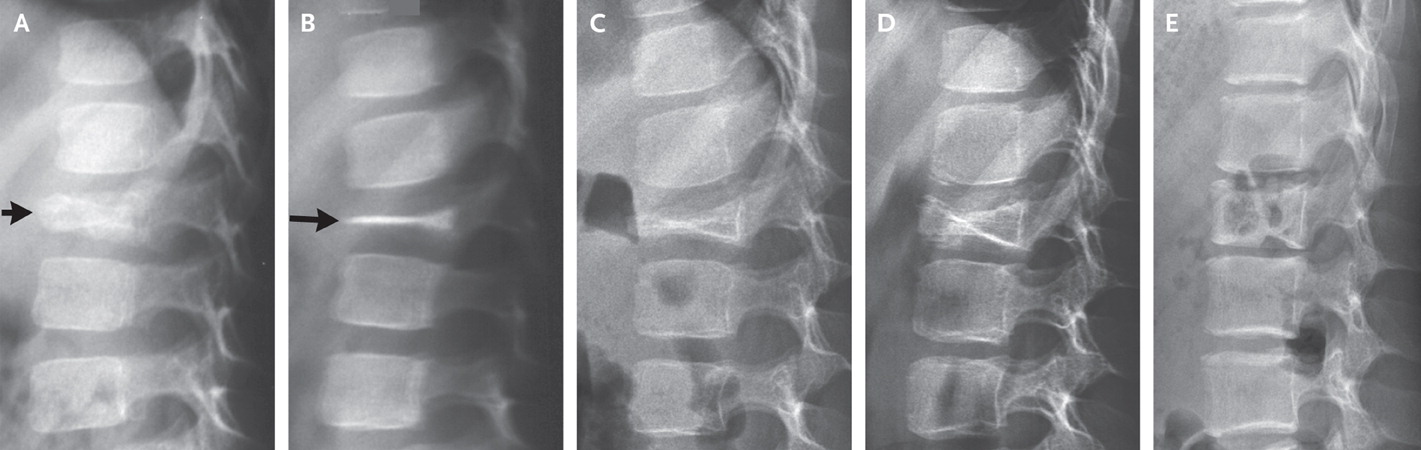

Poi la biologia della vita che è sempre un tesoro di meraviglia ti stupisce. E viene pubblicato un caso I ncui una vertebra completamente appiattita (vertebra Plana) riguadagna la sua altezza quasi naturale. Ora quando mi chiederanno: dottore ma si può recuperare l’altezza della vertera? Potrò rispondere: è difficile, ma è descritto almeno un caso in cui è successo!